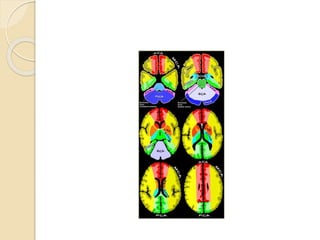

Cerebral Arterial Territory

 MCA-most of lateral hemisphere,

anterior and lateral temporal lobe,Basal

ganglia, insula,

 ACA-Inferomedial basal

ganglia,ventromedial frontal lobes,

anterior 2/3rd medial cerebral

hemispheres, 1 cm supero medial brain

convexity

 PCA-Thalami, midbrain, posterior 1/3of

medial hemisphere, occipital lobe,

postero medial temporal lobe

 AICA- lateroinferior part of pons, middle

cerebellar peduncle, floccular region, anterior

petrosal surface of cerebellar hemisphere

 PICA-inferoposterior surface of cerebellar

hemisphere adjacent to occipital bone,

ipsilateral part of inferior vermis, inferior

portion of deep white matter only

 Superior cerebellar artery-superior aspect

of cerebellar hemisphere (tentorial surface),

ipsilateral superior vermis, largest part of

deep white matter including dentate nucleus,

pons